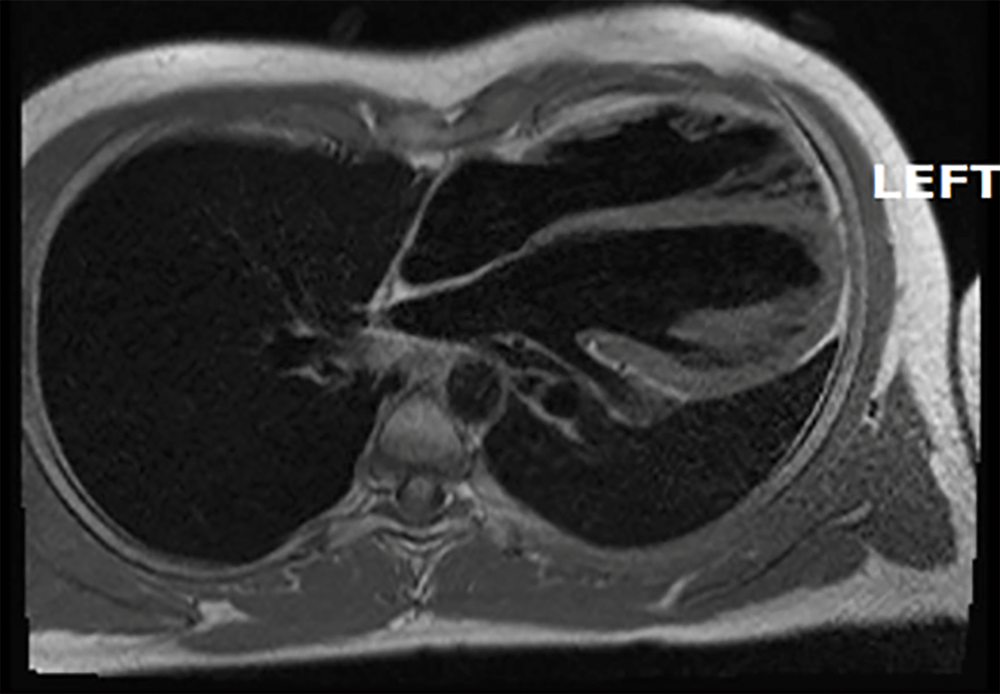

See Figs. 1–3 for a description of the diagnostic criteria.

Figure 2: Cardiac magnetic resonance (axial view, T 1 weighed image) showing that the heart is rotated toward the left (previously unpublished image belonging to the authors)